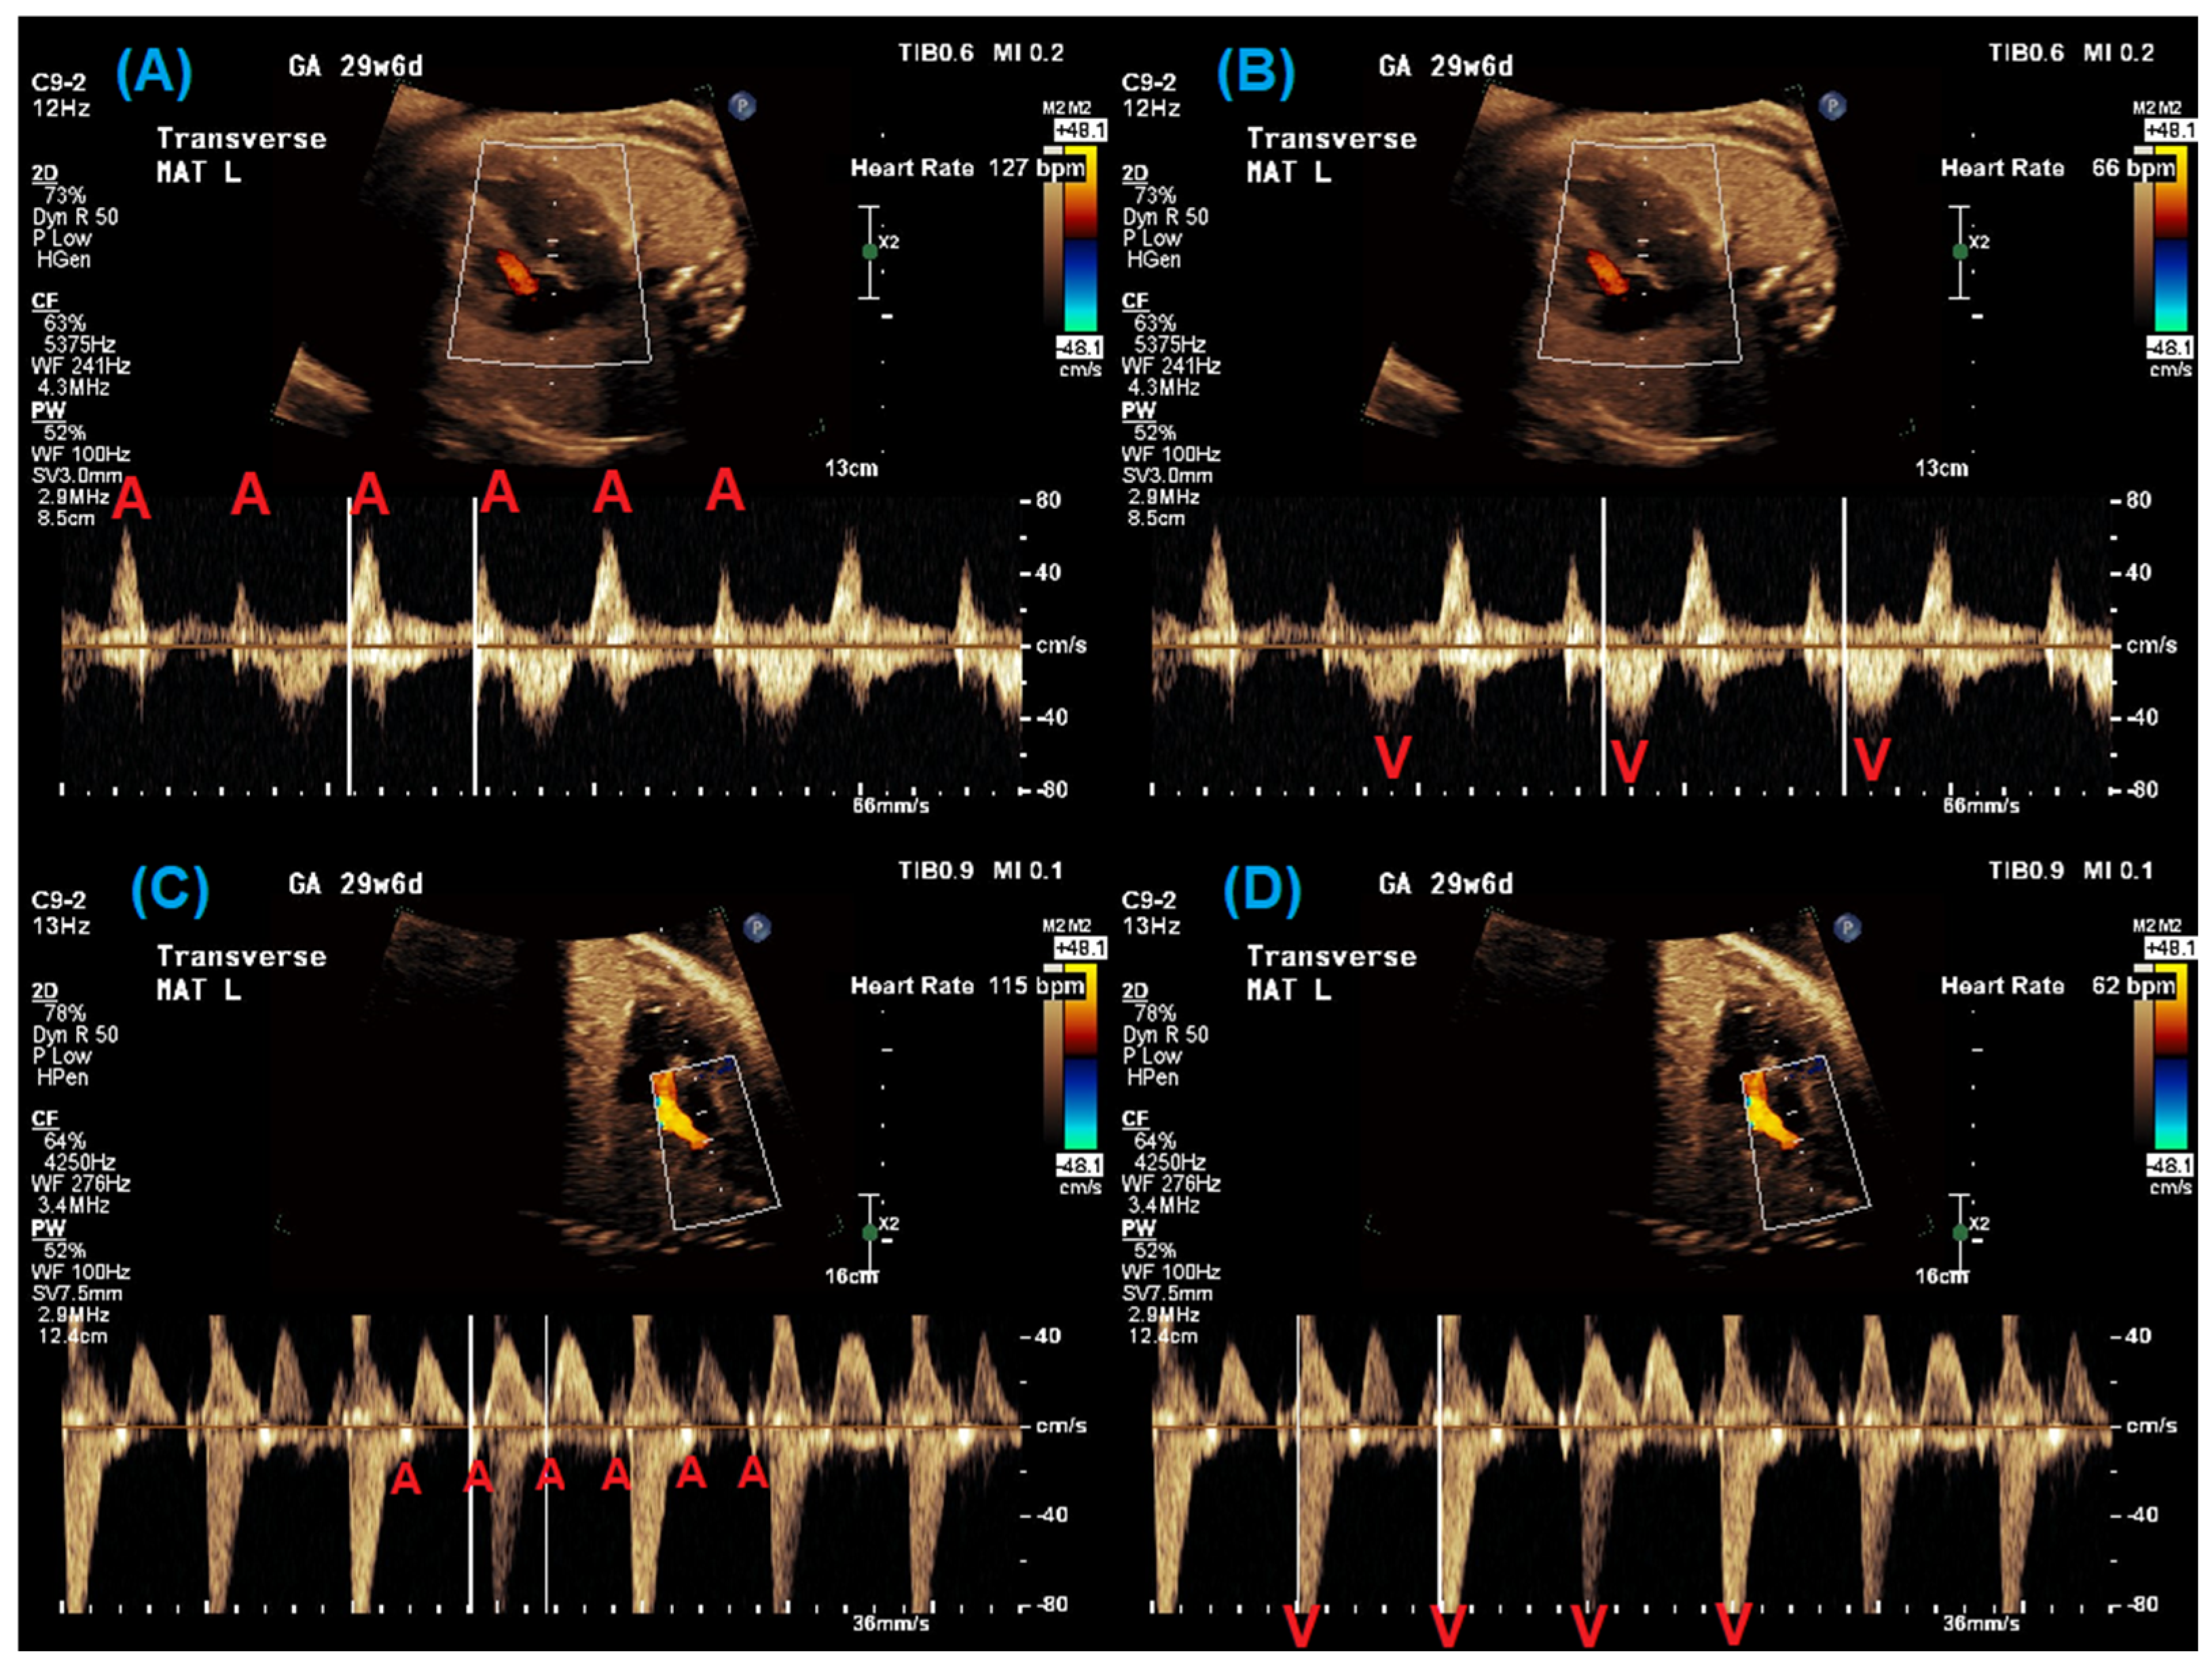

2. Fetal Diagnosis of Long QT Syndrome